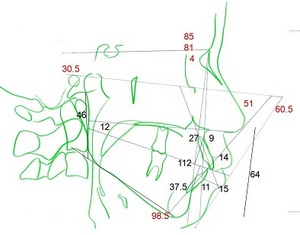

こんな感じで分析しまーす

・上下顎前歯は標準値より前方傾斜してます

・横顔は標準値より突出していることを示す数値です etc…

なお、当医院で一番大切にしているのは上に示したセファロレントゲンの分析です

・上下顎骨の位置関係の把握

・歯列の傾斜

・横顔の評価

などなど、非常に多くの情報が得られます。

患者さんが一番気にされる横顔の変化の予測を立てる際にも大変有効ですので治療計画にもっとっも寄与する検査項目だと思っています。